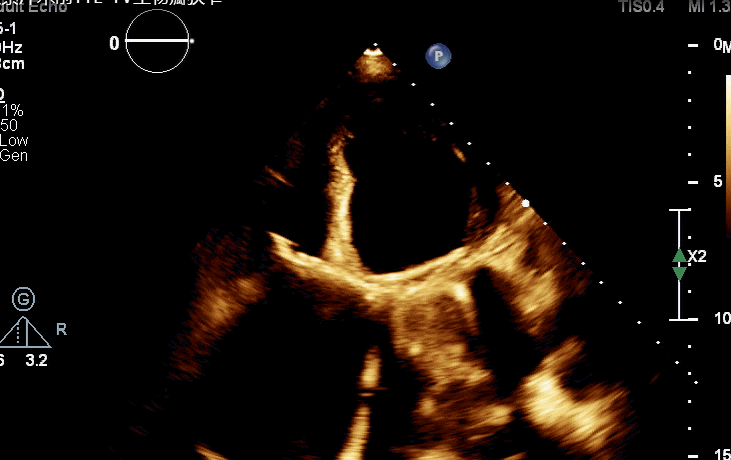

术前TTE-TV生物瓣狭窄

术后TV生物瓣活动良好